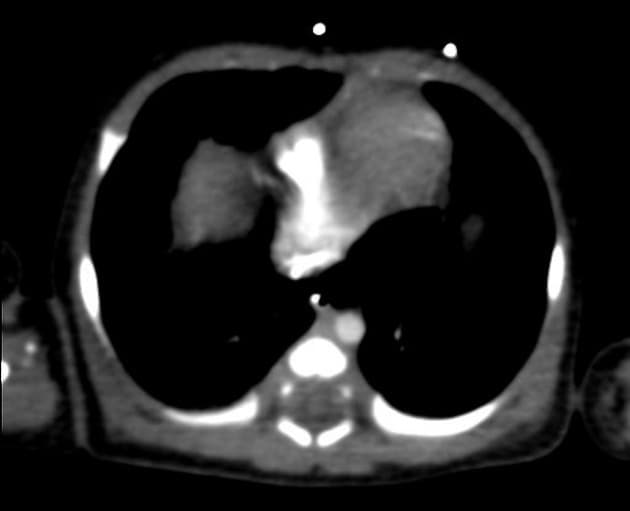

Còn ống động mạch với phình động mạch chủ lên

- Phình động mạch chủ lên (ascending aortic aneurysm) với đường kính trên 50 mm, gây hiệu ứng chèn ép lên động mạch phổi và nhĩ trái liền kề.

- Thông động mạch (patent ductus arteriosus - PDA), kiểu kéo dài, có hình ảnh thuốc cản quang làm sáng động mạch phổi chính, cho thấy tình trạng thông trái-phải (left-to-right shunt).

- Mô nhu phổi hai bên không có bất thường.

Thông động mạch với phình động mạch chủ lên (Patent ductus arteriosus with ascending aortic aneurysm)